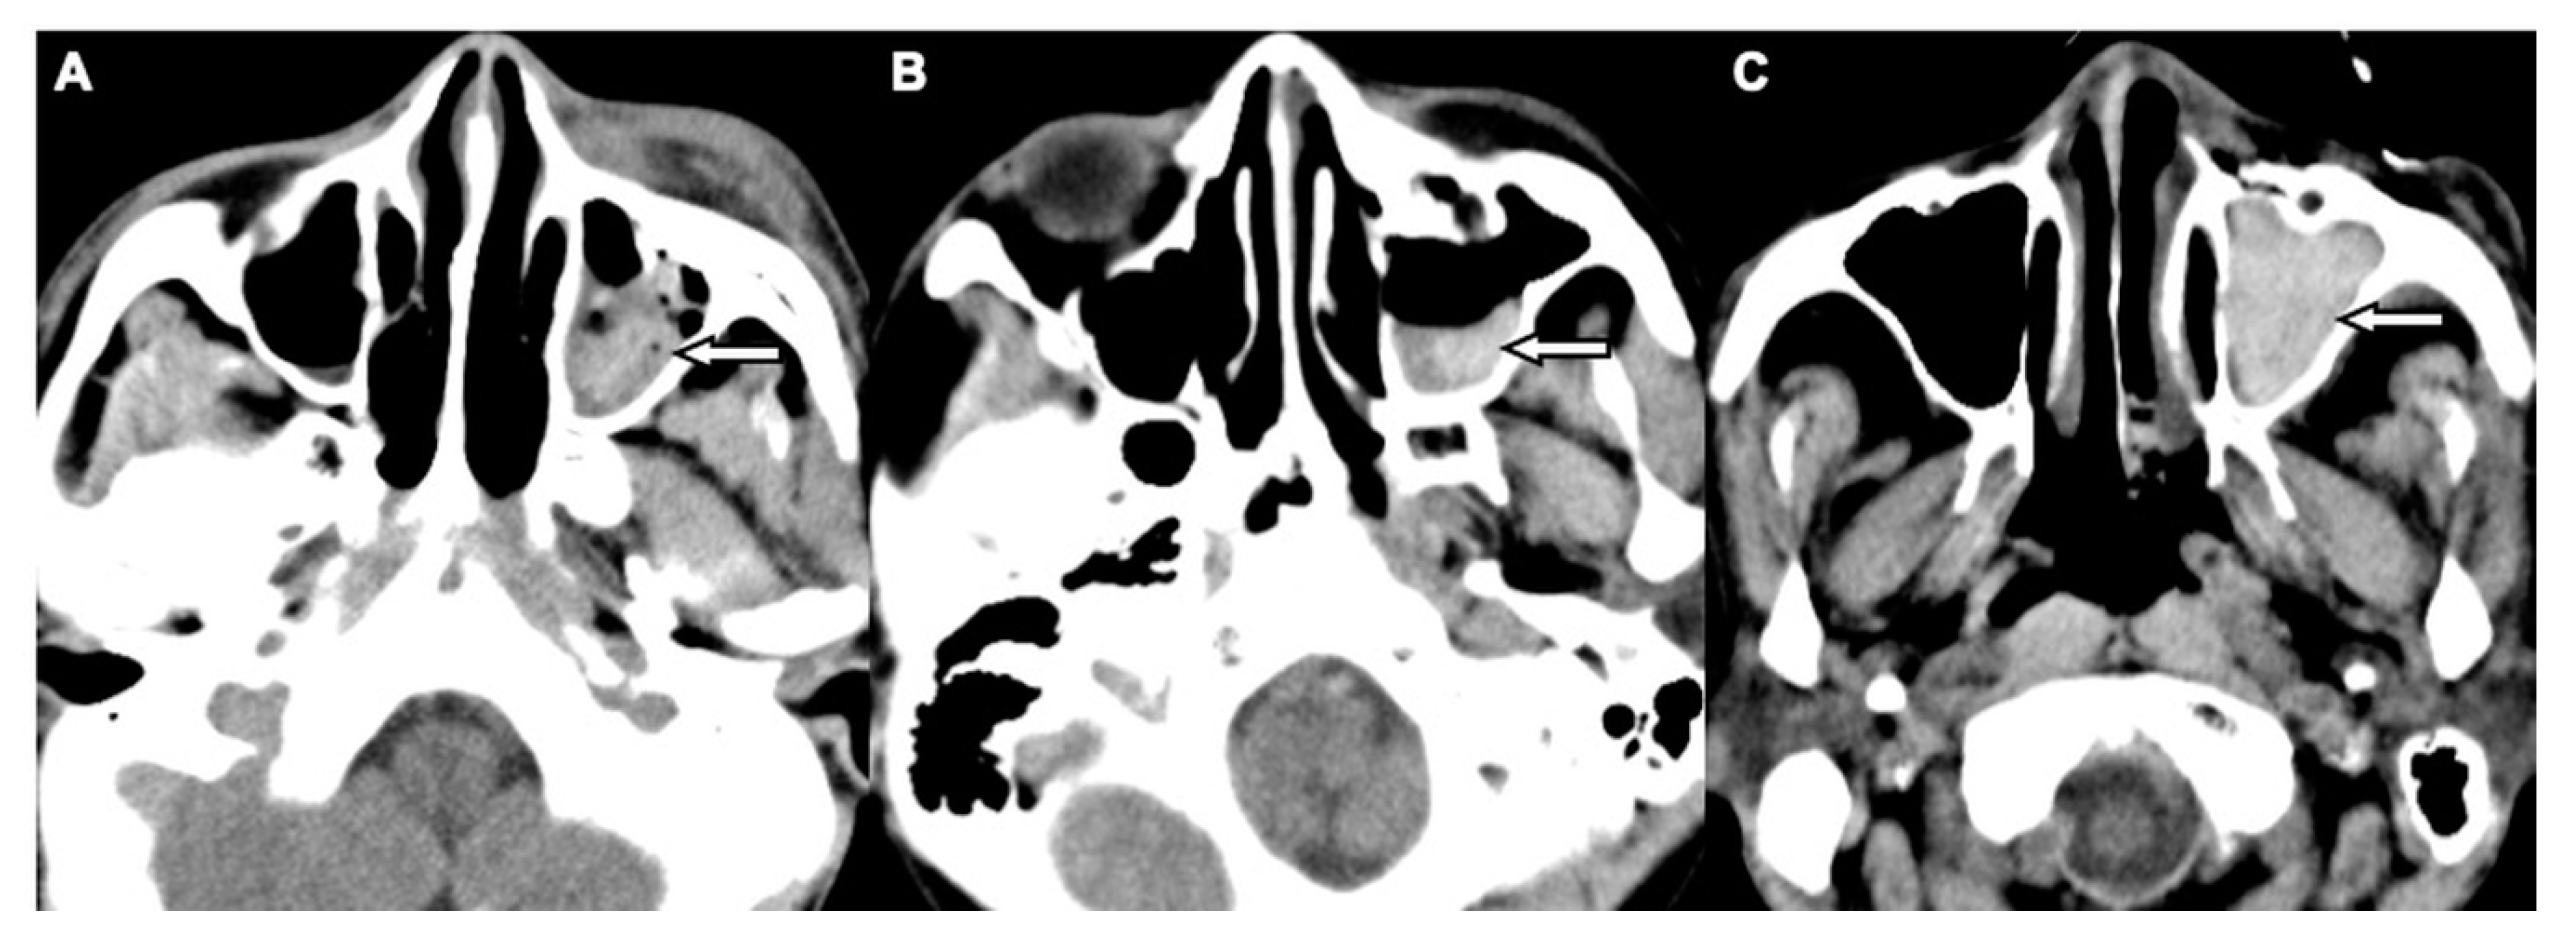

Figure 2. CT images of a 62-year-old female with motorcycle crash-related head trauma and a concomitant left OFF. An axial head CT image (A) and the corresponding coronal facial CT image (B) show inferior extraconal emphysema (straight white arrow) beneath the inferior rectus muscle (black arrow), orbital fat herniation into the maxillary sinus (arrowhead), and the depressed fragments of fractured orbital floor (open curved arrow).

Two board-licensed radiologists (L.D.J. and Y.Y.C.) who were blinded to the patients’ clinical information reviewed only the head CT images by means of consensus. The radiologists were permitted to manipulate the window and level of the images. The CT variables related to the cranium included intracranial hemorrhage (ICH; epidural hemorrhage, subdural hemorrhage, subarachnoid hemorrhage, and intracerebral hemorrhage), and skull fractures. The CT variables related to OFFs included orbital floor discontinuity (Figure 1), gas bubbles entrapped between the floor fragments (Figure 1), inferior extraconal emphysema (Figure 2), orbital fat herniation into the maxillary sinus (Figure 2), and ipsilateral maxillary hemosinus (MHS, Figure 3). MHS was defined as high-attenuation opacity at the dependent portion of the maxillary sinus measuring ≥ 45 Hounsfield units (HU) as the lower limit of attenuation for clotted blood [15]. Since MHS is a relevant indicator used to detect OFFs on CT scans [5,16], we further classified MHS into the following three CT subtypes: (1) Type 1, high-attenuation opacity mixed with mottled gas (Figure 3A); (2) Type 2, air–fluid level (Figure 3B); and (3) Type 3, full opacification of the sinus (Figure 3C).